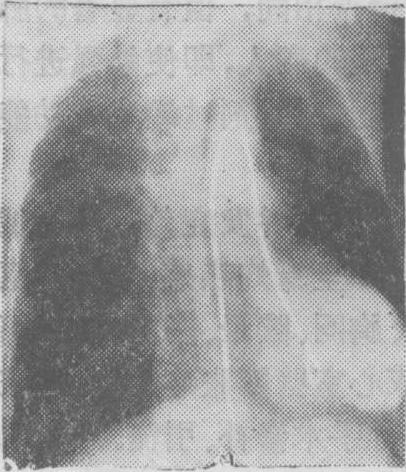

图6 主动脉瓣关闭不全选择性升主动脉造影左前斜位片。图示主动脉和冠状动脉显影,前者略粗,有中量造影剂返流入左心室。

在主动脉窦动脉瘤破裂的病人中,将造影剂注入升主动脉时可见造影剂由主动脉根部进入心腔。主动脉肺动脉间隔缺损时造影剂可由主动脉进入肺总动脉。在动脉导管未闭病人中主动脉显影的同时肺动脉亦显影。在升主动脉或主动脉弓注射造影剂还可显示主动脉动脉瘤(图5)、主动脉瓣上狭窄、主动脉缩窄和主动脉弓各分支的病变。主动脉瓣关闭不全时在升主动脉中部注射造影剂可显示造影剂反流入左心室(图6)。